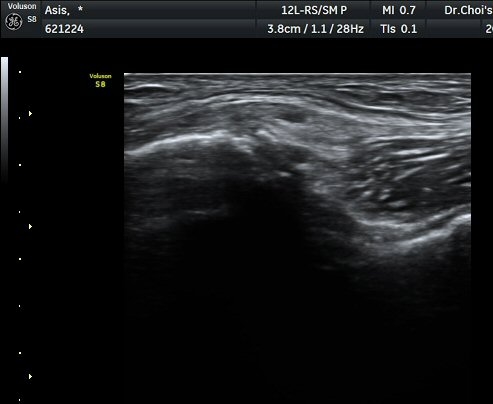

Àü»óÀå°ñ±ØÀÇ ºñ½ºµëÇÑ Á¾´Ü¸é°Ë»ç¿¡¼­ ¼­ÇýºÎ  Àδ밡 ºÎÂøµÇ´Â Àü»óÀå°ñ±ØÀÇ °ß¿­°ñÀýÀÌ

°üÂûµÇ°í(±×¸² 1) ¿ÜÃø´ëÅð±ÙÇǽŰæÀÇ ºÎÁ¾ÀÌ °üÂûµÊ(±×¸² 2, 3). Àü»óÀå°ñ±Ø Ⱦ´Ü¸é°Ë»ç¿¡¼­